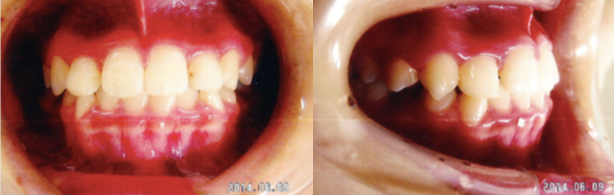

出っ歯(上顎前突)

出っ歯の治療方法は子どもと大人で違います。子供の場合は、あごの成長を止めることで、

バランス良い歯並びに調整します。大人の場合は、歯を移動させることで、出っ歯を改善させます。

治療前

治療後